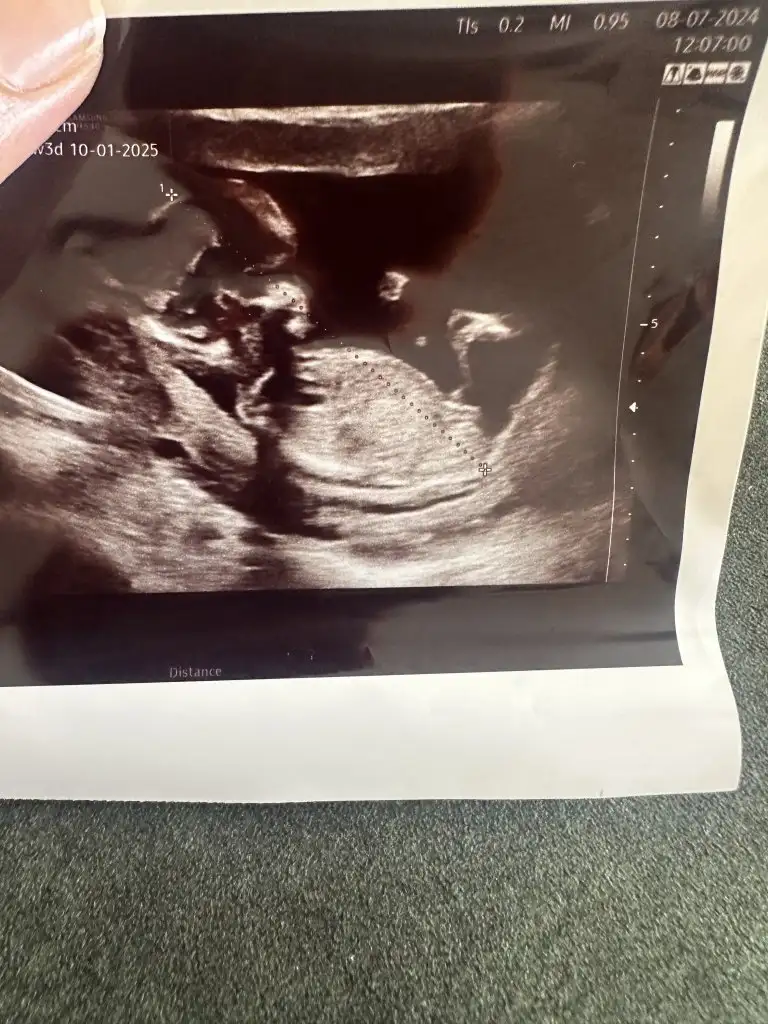

Rica etsem bana da bakabilir misiniz karından ultrason

Lutfen bana tahminde bulunabilir misin karından çekilmiş bir ultrason